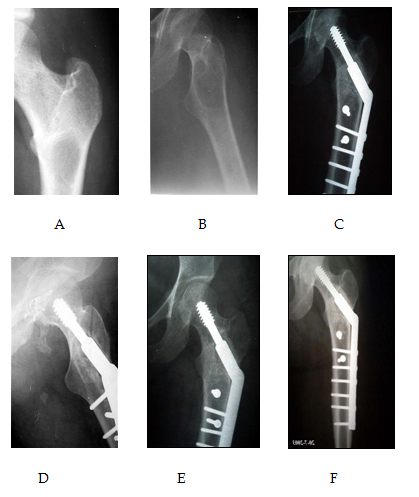

Excluded from this study any patient who already developed pathological fracture. Different types of fixation either surface plating (dynamic hip screws) (Figure 3 & 4) medullary (Gamma nails) (Figure 5) or external fixation in cases unsuitable for surgery (Figure 6) were used according to the type and the site of the deformity. In tibial cases, we used the tourniquet without blood evacuation in the limb.

Figure 6 (A) shows an x-ray with post traumatic infected interlocking nail and partial healing of the fracture. (B) After debridement of the infection, removal of the nail with the risk of sustaining a pathological fracture through a defect in long bone. A prophylactic external fixator was applied to avoid a pathological fracture.